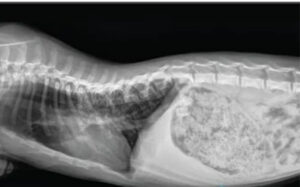

Chẩn đoán: chụp X-quang vùng ngực để phát hiện đốt sống dị dạng → dẫn đến liệt chi sau.

Biến dạng đốt sống ở mèo